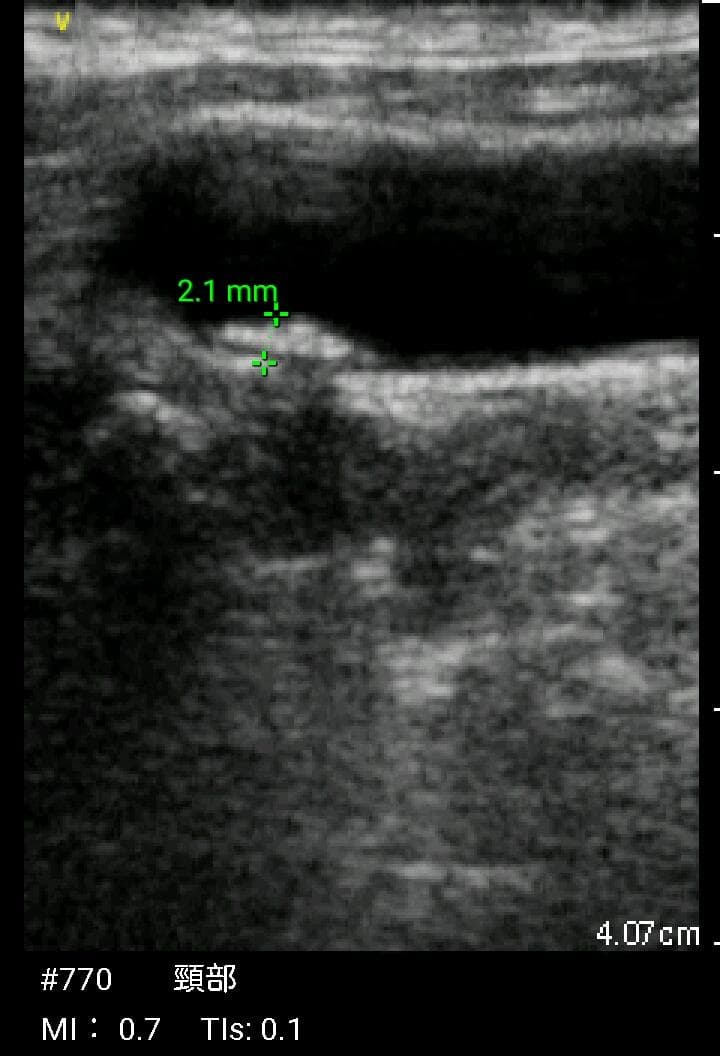

おわかりになる方のみの購入をお願いいたします実際に実施した写真をあげました正常肝臓、胆石症、頸動脈プラーク、同じく頸動脈プラーク、Mrの収縮期、同じくM弁の開放期とA弁の開放期、腹部大動脈瘤、正常の頸動脈、甲状腺右葉の結節、前立腺肥大画像の描出は条件によりますがご検討をお願いいたします経年変化、使用に伴うスレや傷などがあります機能に問題はありませんスキャンは心血管、腹部、体表に対応します外部接続端子のカバーが一部壊れていますが蓋は閉まりますバッテリーはフル充電されますが劣化はあると思います医療用モニタリング機器 Vscan Extend、GE- モデル名: Vscan Extend- ブランド: GE- 色: ホワイト- 機能: 医療用モニタリング機器ご覧いただきありがとうございます。セブンプレミアム 耳が痛くなりにくい やわらかマスク385枚。